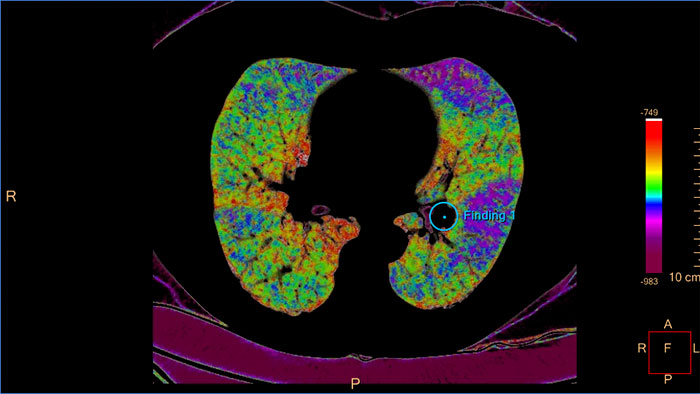

Allows retrospective use of spectral data that was saved as an SBI. Allows reviewing of spectral data and identification of most relevant result to be launched into the conventional CT application for routine work – even for applications that were not developed to support Spectral functionality.

IQon Spectral CT Functionality

IQon Spectral CT is the only scanner to offer CT Spectral Light Magic Glass and CT Spectral Magic Glass on PACS, helping radiologists review and analyze multiple layers of spectral data at once, including on their PACS.

The spectral viewer is optimized for analysis of spectral data sets from the IQon Spectral CT Scanner. Obtain a comprehensive overview of each patient quickly and easily, quantify quickly, and assist in diagnosis. It is designed to accommodate general spectral viewing needs with additional tools to assist in CT images analysis.